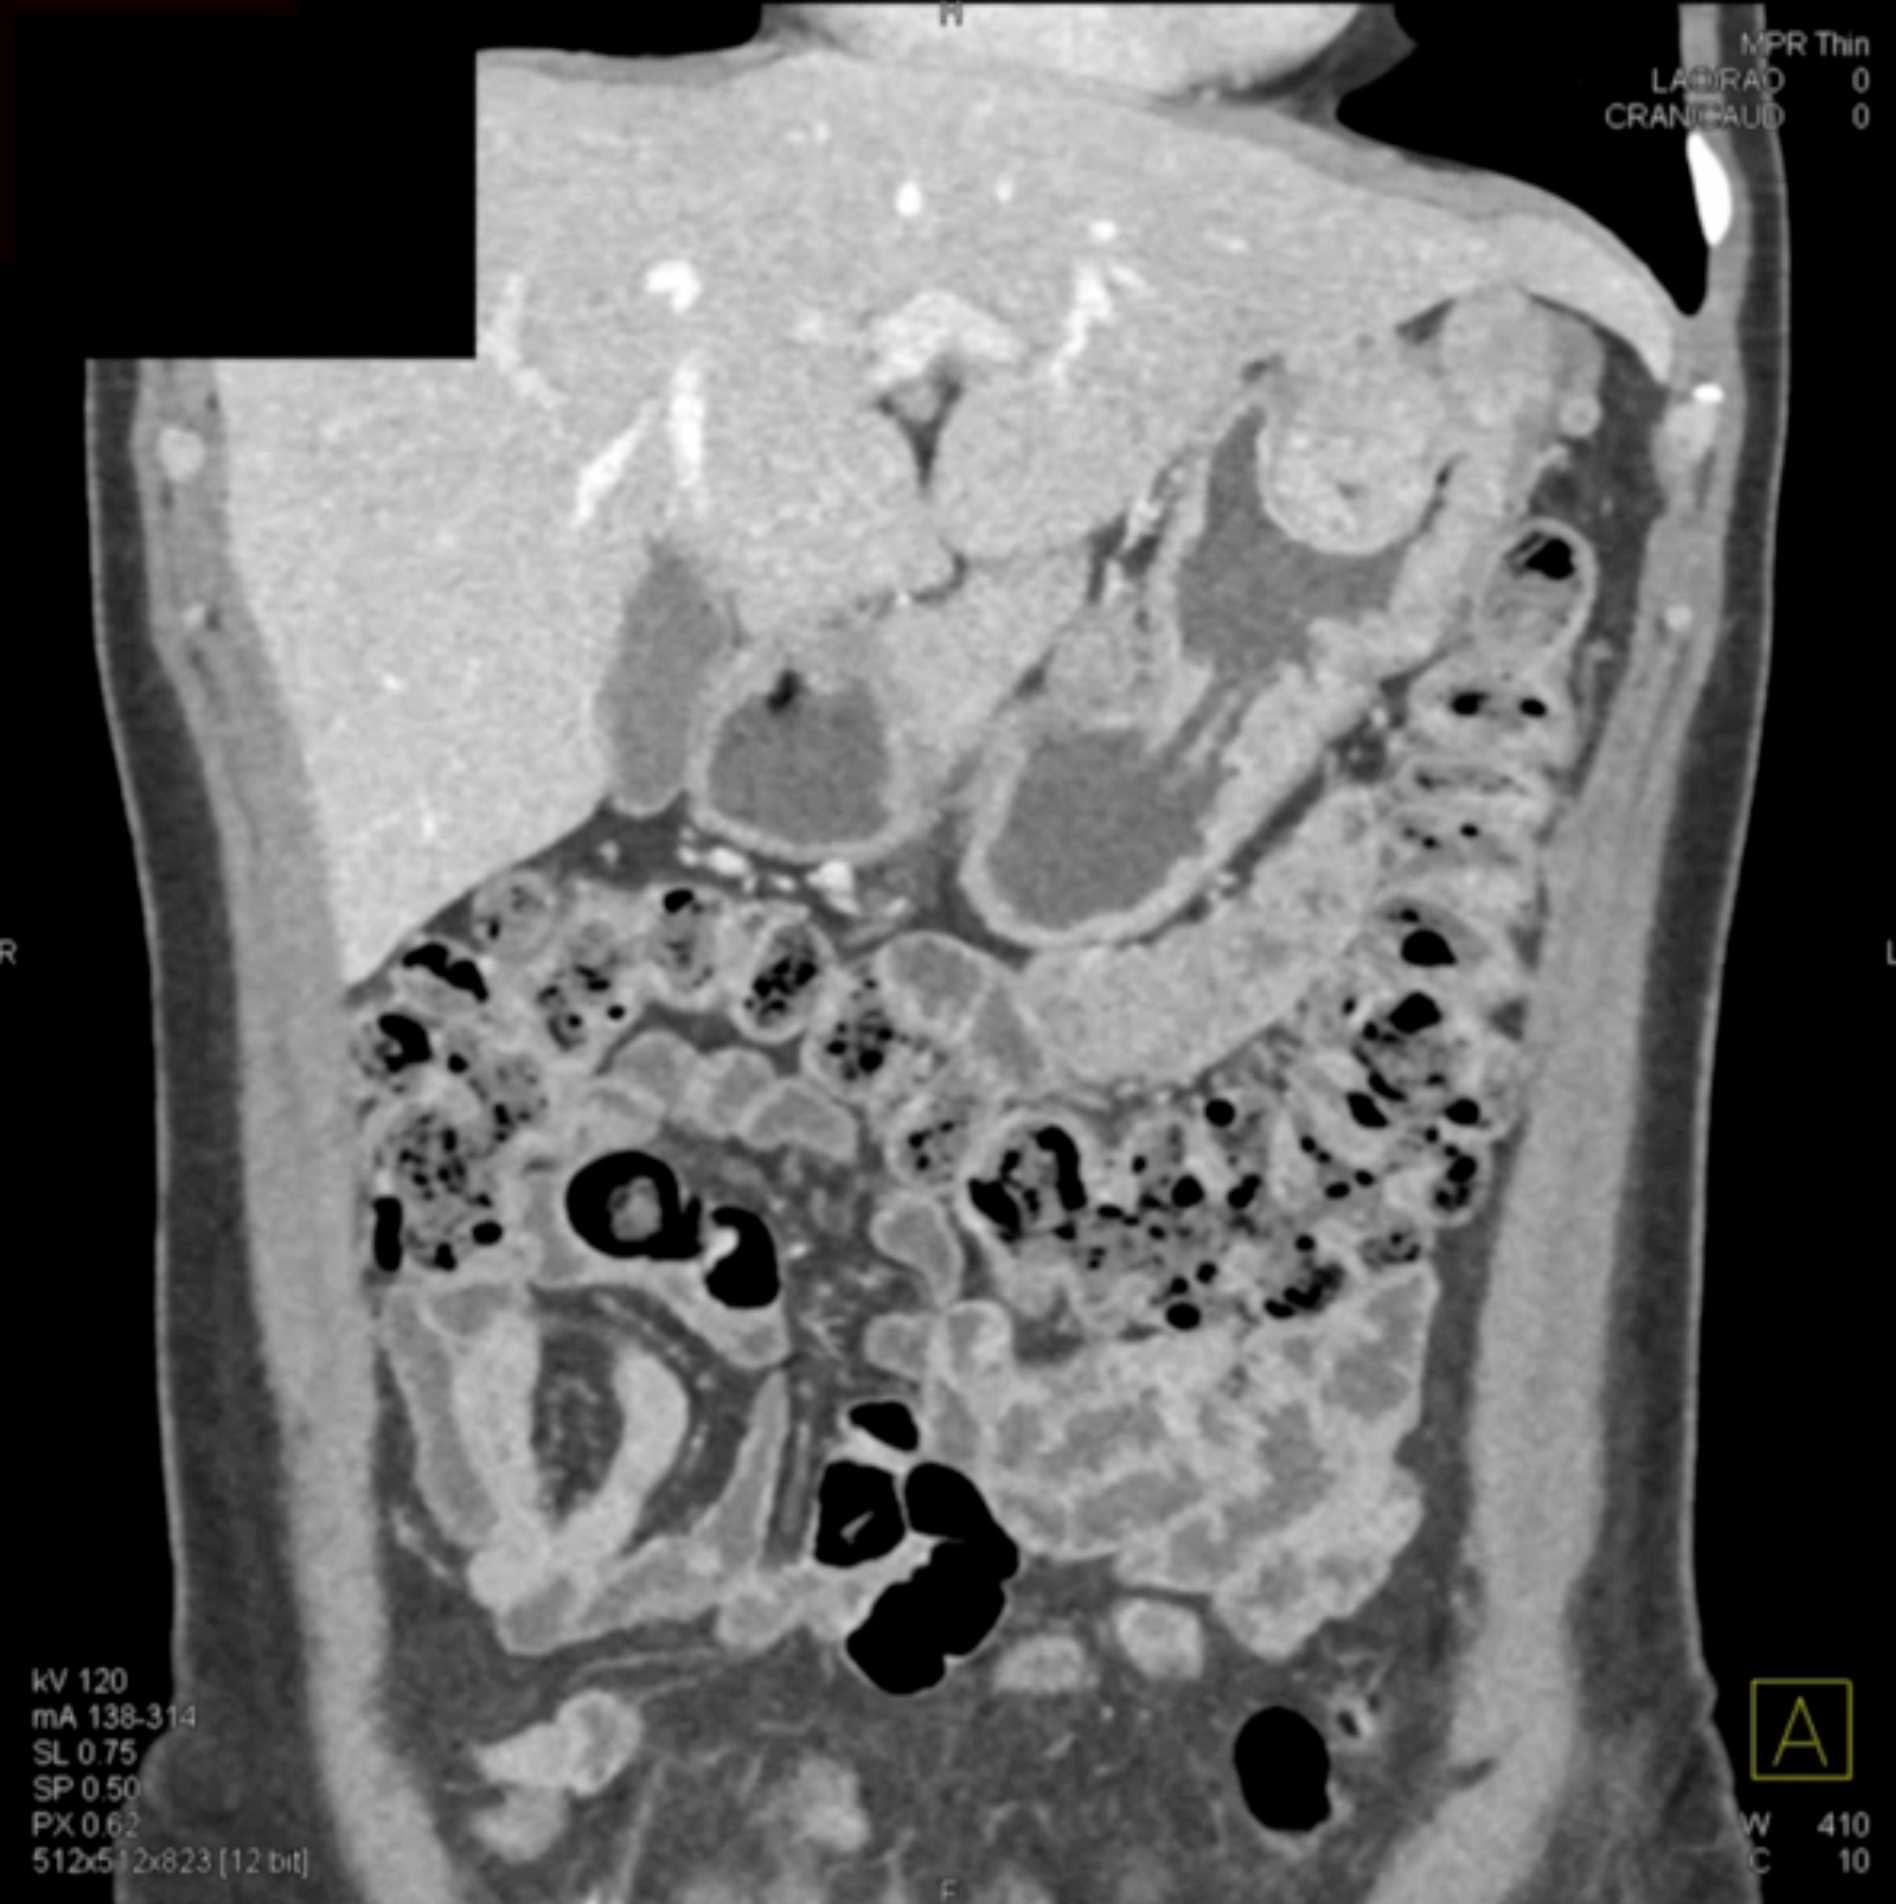

Multiple Gastric GIST Tumors with Spread to Nodes (Carney-Stratakis Syndrome)